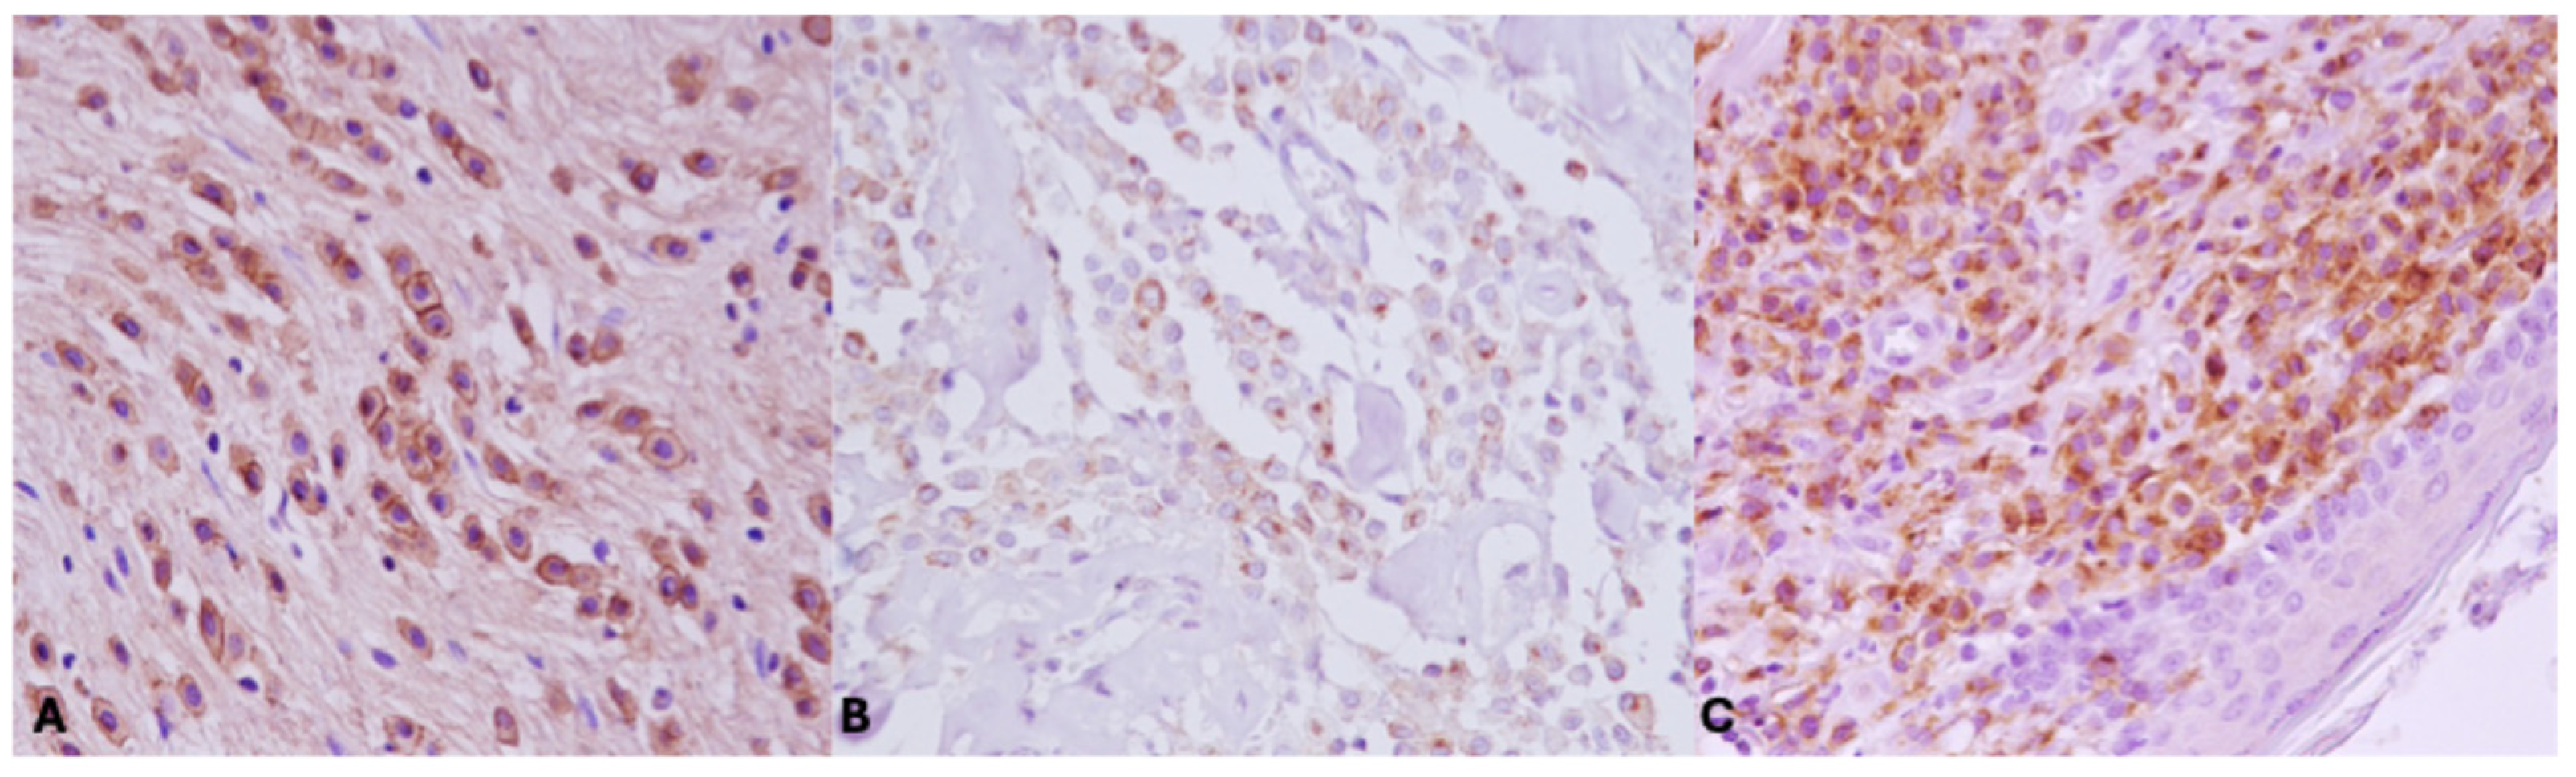

2.2. Immunohistochemistry and Evaluation of KIT Staining Patterns